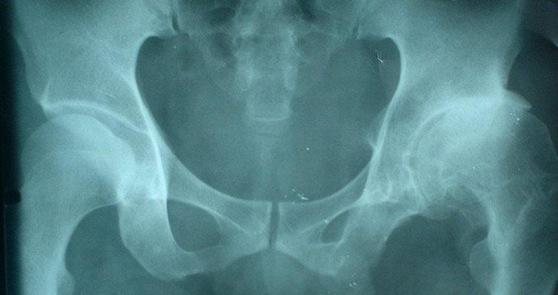

如何治疗三期股骨头坏死

如果得了股骨头坏死没有及时治疗,会给患者的身体造成极大的伤害,很多患者都是因为没有留意自己的身体,结果恶化到三期,导致治疗起来相当的费劲。

那么三期股骨头坏死该如何治疗呢?济南股骨头医院的专家指出一般对于三期股骨头坏死的治疗常见的有三种方法: